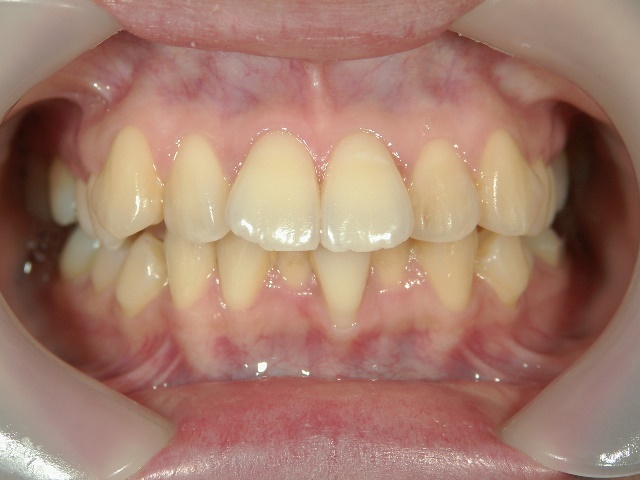

矯正歯科(全顎ワイヤー矯正)治療後

矯正歯科 治療後